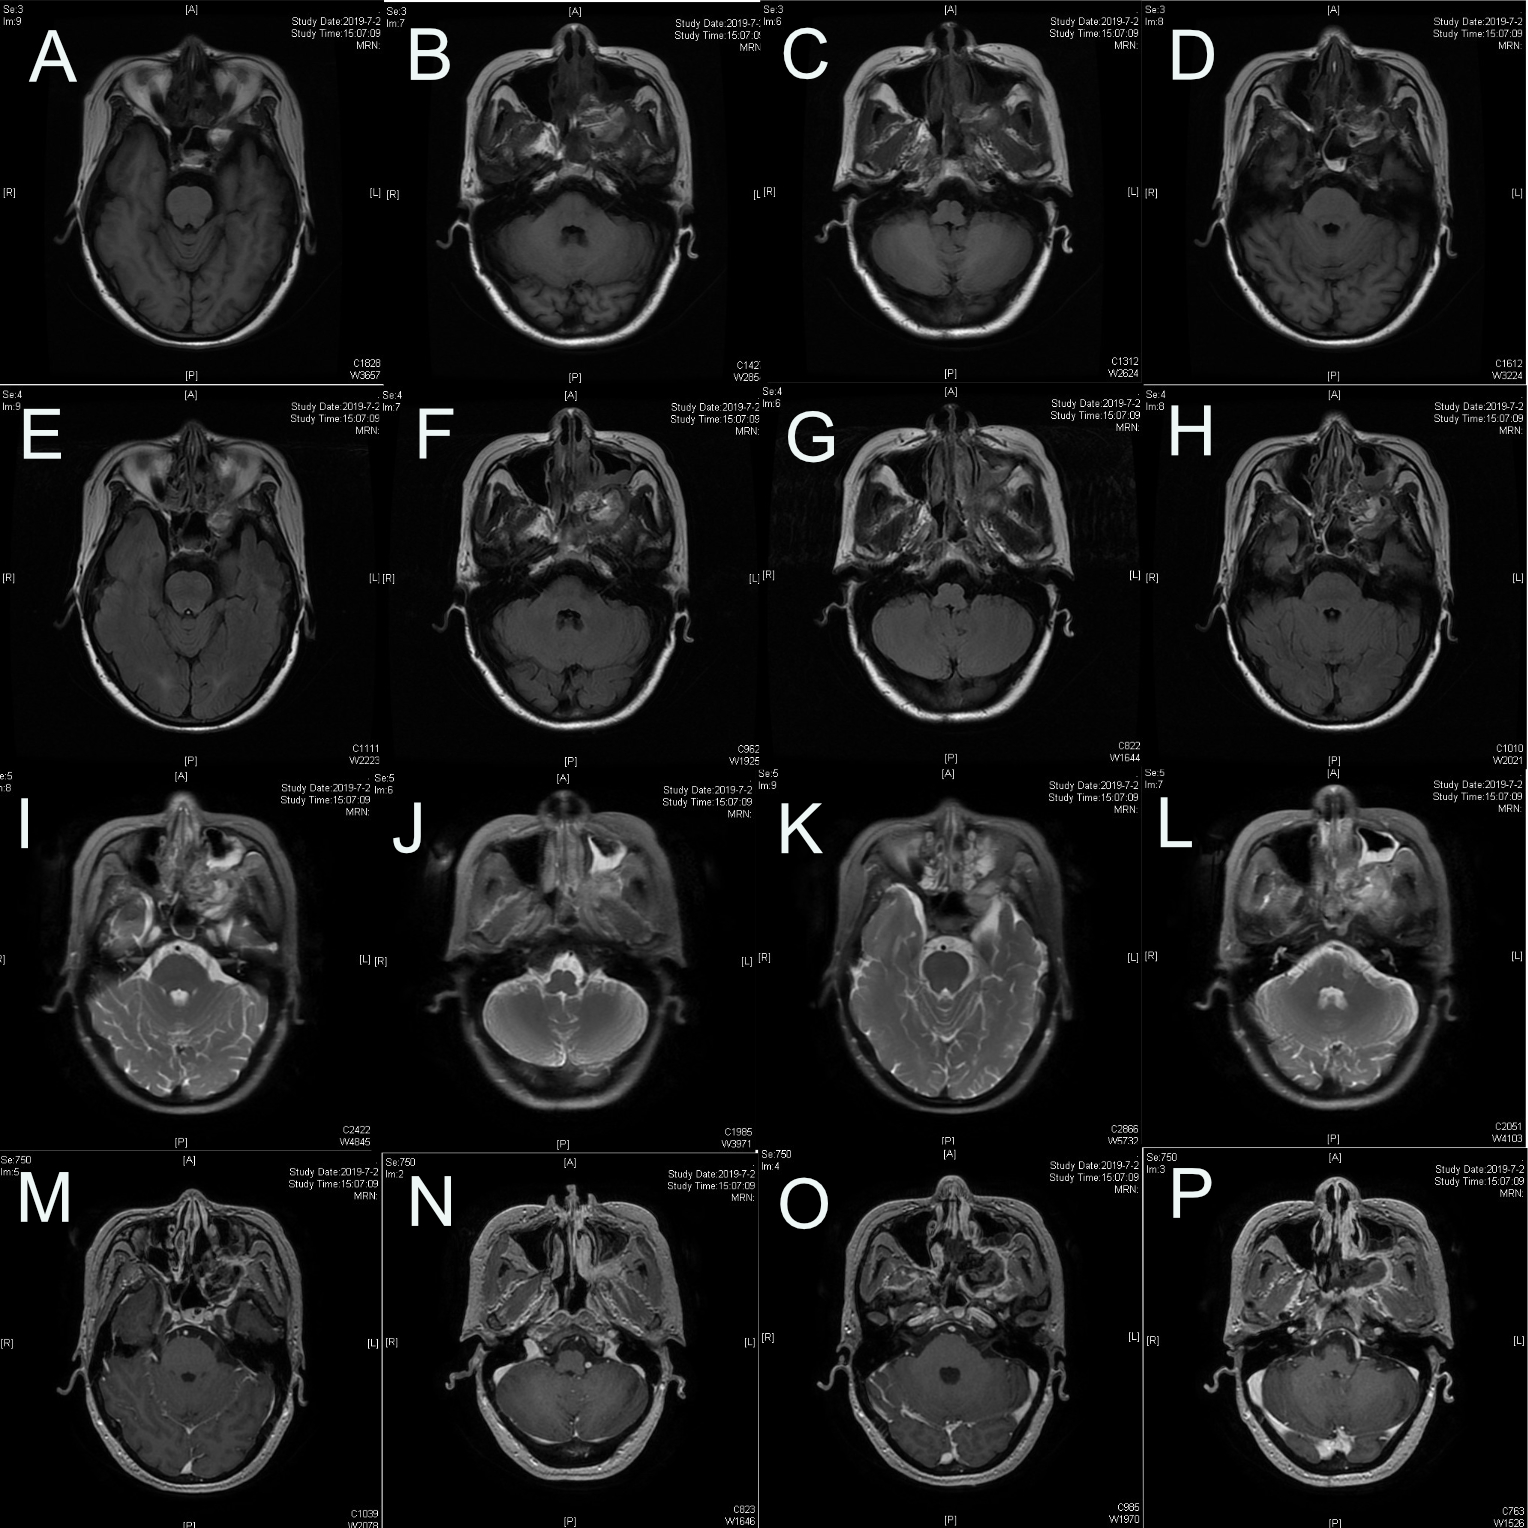

图1.蝶鞍区CT:左侧颅底见梭形软组织密度影,大小约3.7*1.9㎝,周围骨质受压变薄。

图2.PPF内肿瘤侵犯上颌窦后壁以及颞下窝,部分肿瘤向中颅底侵犯。

图3.诊断:左侧PPF肿瘤(术后病理:神经鞘瘤)